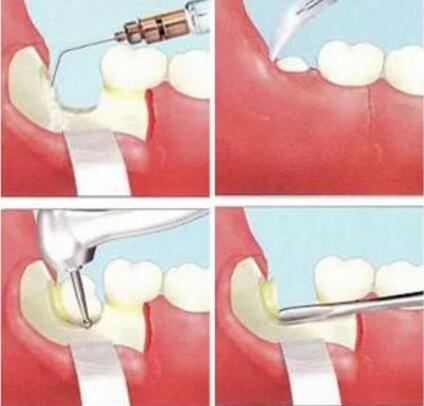

智齒拔牙過程

1、現在的拔牙不再是“錘、劈、敲”等方式,而是使用高速渦輪機、微創拔牙刀等器械,作為(wei) 專(zhuan) 業(ye) 口腔醫院,愛康健口腔有多種專(zhuan) 業(ye) 拔牙器械,可以讓拔牙變得簡單,減輕大家對拔牙的恐懼。

3、智齒拔牙微創、**,通常需要先消毒進行麻醉(打麻醉針時有一兩(liang) 秒輕微刺疼),等到麻醉發生作用才開始拔牙,所以拔牙的時候你能感受到,但是不疼。所以大家可以放心。